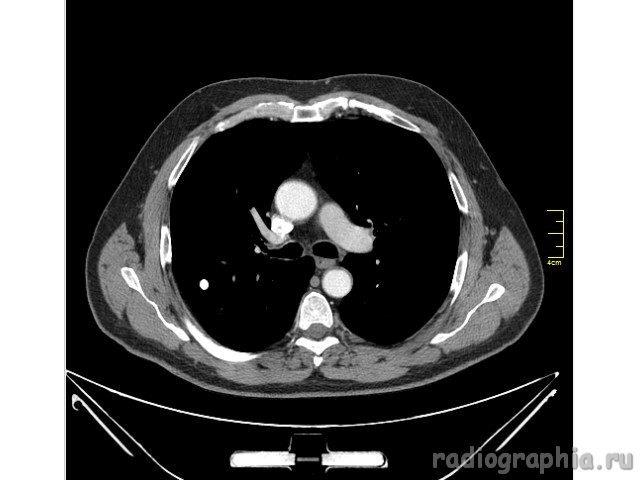

Одиночный узел правого лёгкого.

На рутинном снимке ОГК, был выявлен одиночный узел; по протоколу выполнили КТ. Какое было бы ваше заключение; и как бы Вы поступили если у вас нет возможности выполнять КТ?